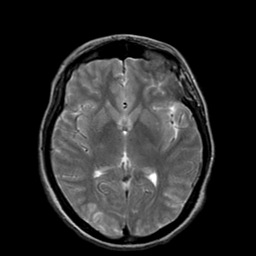

Hypertensive Encephalopathy, overlay -- Slice #12

[Home][Help][Clinical] Slice 12